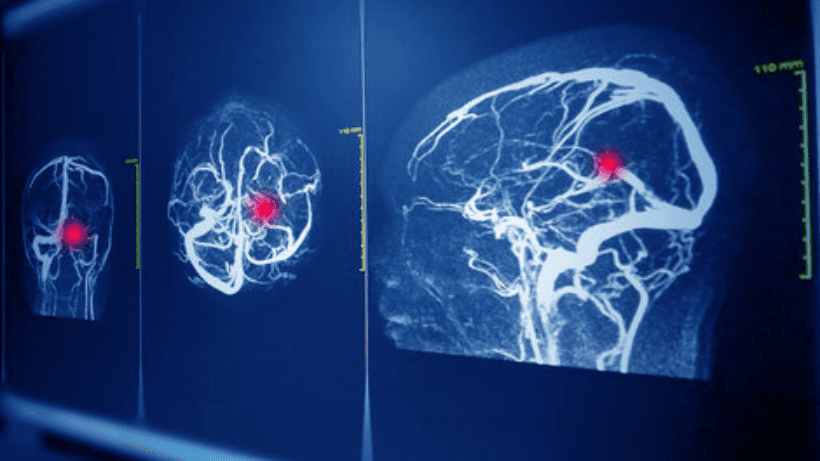

A. Imaging Tests: These are like the detective tools doctors use to see what's going on inside your brain.

- CT Scan: It's like a high-tech X-ray that gives doctors detailed pictures of your brain. It's quick and often the first choice for diagnosis.

- MRI: This is another imaging method that uses magnets and radio waves to create detailed brain images. It's especially good at showing smaller aneurysms.

- Cerebral Angiography: Think of this as a road map of your blood vessels. A special dye is injected into your bloodstream, and X-rays are taken to pinpoint any aneurysms.